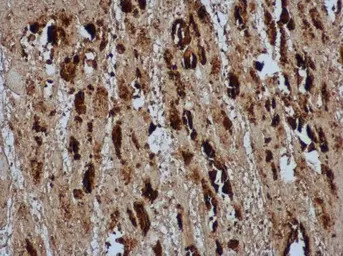

EV71 VP2 antibody detects EV71 VP2 protein in EV71 infected mouse skeletal muscle by immunohistochemical analysis. Sample: Paraffin-embedded EV71 infected mouse skeletal muscle. EV71 VP2 antibody [GTX132340] diluted at 1:500

Antigen Retrieval: Citrate buffer